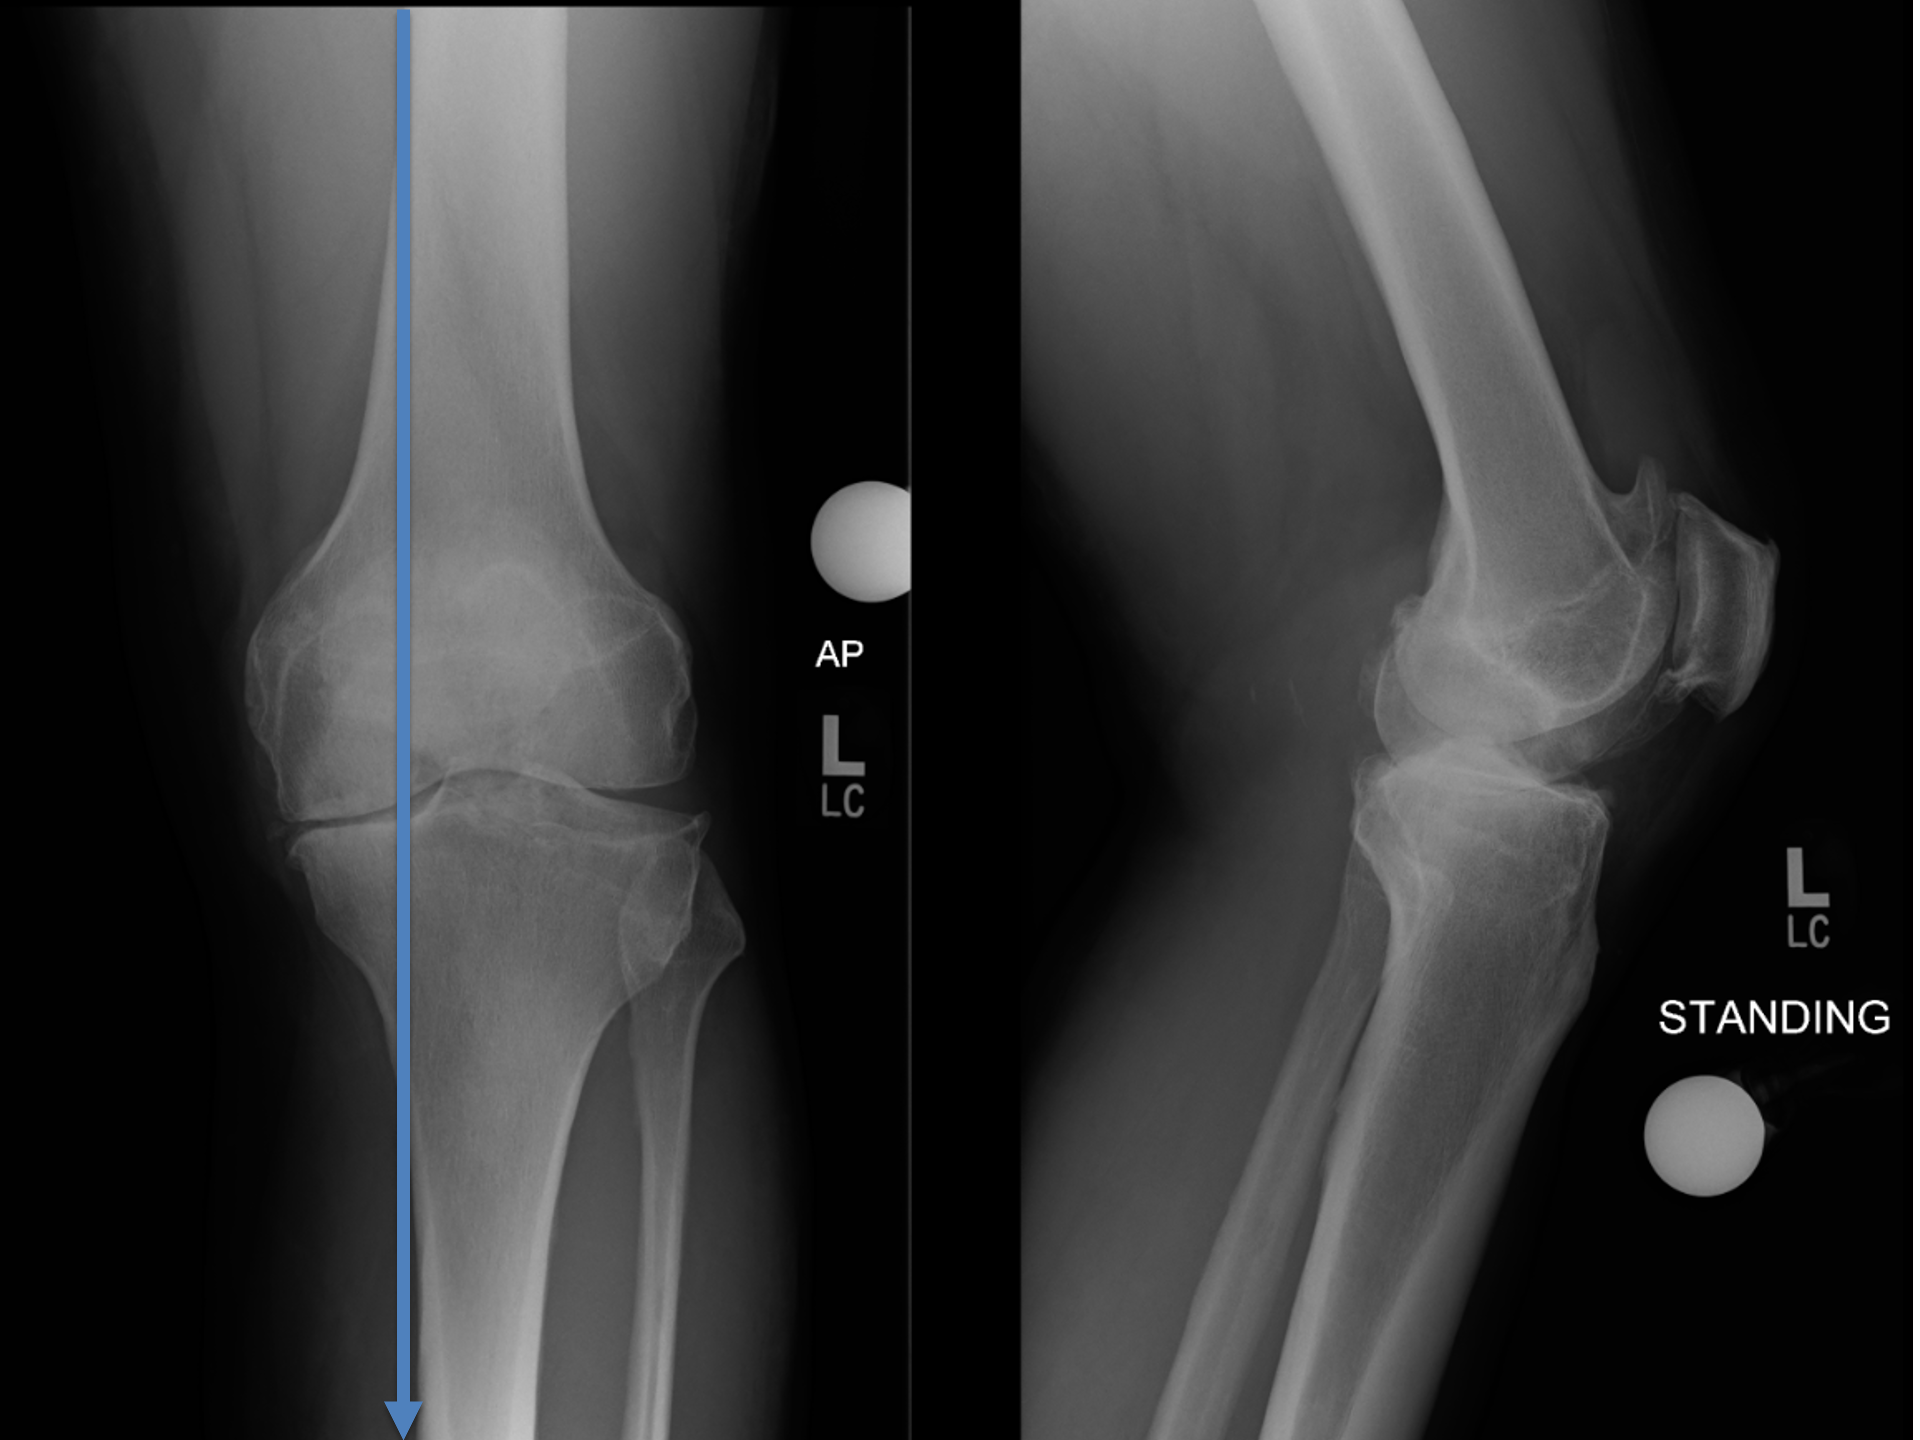

The subtle deformity here is on inside of the tibia..

(or shin bone / the bottom half of the knee joint)

People often say 'I've always been bow-legged'..

Higher peak force..

Through the inside of the knee

3 Million steps / year

Over a lifetime..

Inevitably leads to..

Intact ligaments restrict cartilage loss to a characteristic pattern that guides treatment.